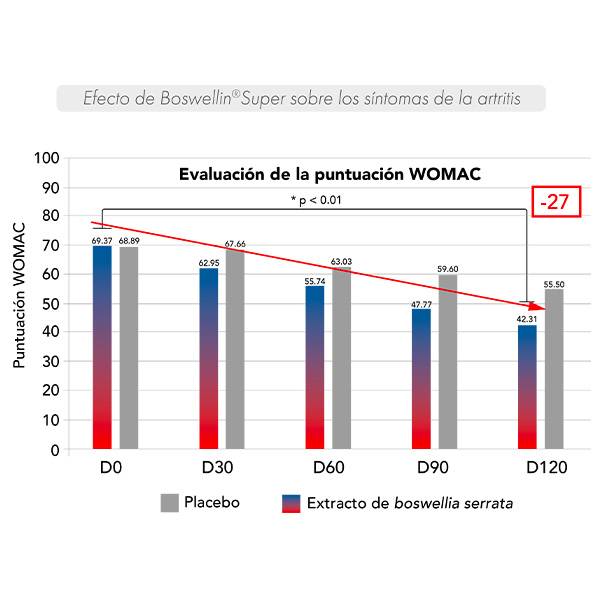

Se realizó un ensayo clínico doble ciego controlado con placebo en 48 personas diagnosticadas de artrosis de rodilla durante 120 días.

Los síntomas asociados a la artrosis se evaluaron mediante un cuestionario para los participantes (WOMAC**).

Los síntomas de la artritis disminuyeron progresivamente desde los 30 días hasta los 120 días.